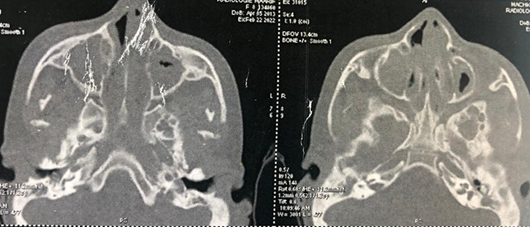

A CT scan of the nasal cavities showed a hypodense,

homogeneous, confluent process filling the maxillary sinuses, frontal sinuses,

ethmoidal cells, sphenoidal sinus and nasal cavities, in favor of bilateral

nasosinus polyposis. There is also a significant hypertrophy of the posterior

soft tissues of the cavum, leading to obstruction of the upper airway (Figures1 and 2).

Figure 1: Axial- section CT scan of

the nasal cavities showing total filling of the maxillary, ethmoidal, frontal

and sphenoidal sinuses and nasal cavities.